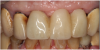

Figure 3 shows a ti-base connection, narrow emergence profile of the zirconia abutment (pink characterization), and final abutment with margins that were computer-generated and computer-manufactured to reflect the appropriate soft-tissue architecture for the patient. As shown in Figure 4, the abutment was seated and torqued to 25 Nm, allowed to rest for 10 minutes, and torqued once again to 25 Nm. The crown was tried in, fit was verified, and occlusion was established. This particular patient was concerned that the implant crown and implant would not look natural. Before beginning the single-tooth replacement with implant dentistry, a diagnostic wax-up and photographic imaging were employed to help develop a natural-looking provisional during the osseointegration phase. A treatment plan was developed and presented to the patient for considering cosmetic dentistry for tooth Nos. 6 through 11. The patient was still apprehensive and chose to begin therapy for only tooth No. 8. Since the final seat date, the patient has been very satisfied with the results of the single-tooth therapy and has committed to completing the cosmetic dentistry services for tooth Nos. 6 through 11.

Fig 4. Seated abutment (left) and crown try-in (right).

Figure 4